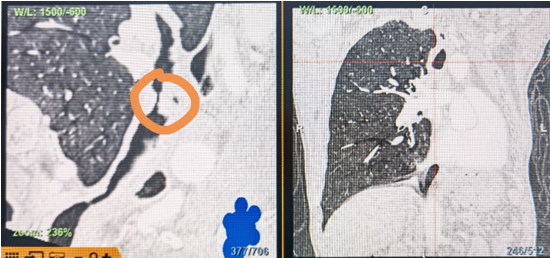

時(shí)間就是生命!了解患者病情后,歐陽(yáng)海峰立刻啟動(dòng)氣道梗阻緊急救治通道,協(xié)調(diào)院前轉(zhuǎn)運(yùn),急診快速入院流程。凌晨患者入院胸部CT顯示,現(xiàn)存唯一的呼吸通道在右主支氣管處,狹窄處僅約3毫米,患者命懸一線!

運(yùn)用呼吸介入技術(shù),軟硬鏡結(jié)合快速開通氣道,是患者目前唯一可行的治療方案,手術(shù)刻不容緩!但存在麻醉后氣道完全塌陷閉合、大出血、窒息等巨大風(fēng)險(xiǎn)?;颊叽饲敖舆B轉(zhuǎn)診3家醫(yī)院,均建議保守支持治療或轉(zhuǎn)院。歐陽(yáng)海峰詳細(xì)了解患者病史,全面評(píng)估影像檢查結(jié)果后,決定盡快進(jìn)行手術(shù),組織醫(yī)護(hù)團(tuán)隊(duì)對(duì)患者進(jìn)行持續(xù)密切監(jiān)測(cè),充分保障其術(shù)前安全。